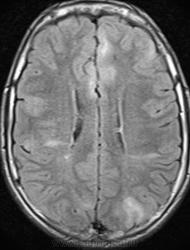

Это болезнь Бурневилля - одна из форм факоматозов?

Да, это болезнь Бурневилля-Прингла, один из видов факоматоза. Врожденное заболевание, развивается из-за нарушений в одной из хромосом.

Пару раз встречала и раньше. Но у нас "взрослая" больница, может быть в детской больнице их больше.

На УЗИ выявлены множественные ангиомиолипомы почек.